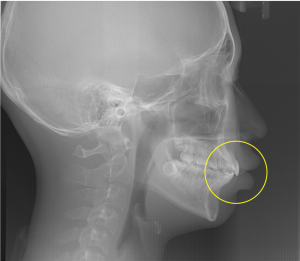

※頭部X線規格写真とその分析値

頭部X線写真を用いた詳しい分析の結果、下あごがやや後ろに位置している骨格の特徴があることがわかりました。また、顔全体のバランスは標準的である一方、上下の前歯がやや前に出ている傾向が確認されました。

頭部X線写真の中で、黄色の線で囲った部分に注目すると、上の前歯が前方に突出している様子が視覚的にも確認できます。